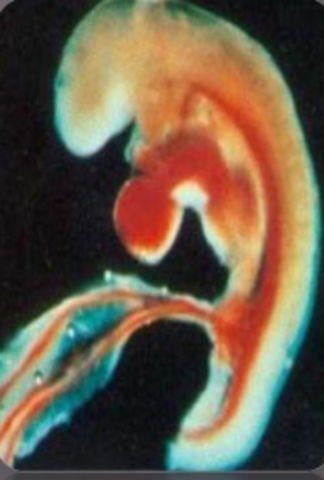

• Gastrulación- DÍA 15

Gastrulación- DÍA 15

Ocurre después de la formación de la blástula.

Forma 3 hojas embrionarias:

Ectodermo: forma parte de la epidermis

Mesodermo: forma la parte superior de la capa que crece hacia el interior en la blástula

Endodermo:células internas .

-Tiene una cavidad central (arquénteron) y un orificio (gastrocele) que comunica el arquénteron con el exterior

La gástrula posee una cavidad llamada celoma.

El gastrocele origina el ano y en el lado opuesto la boca.

-La gástrula es triblásica celomada deuterostomada